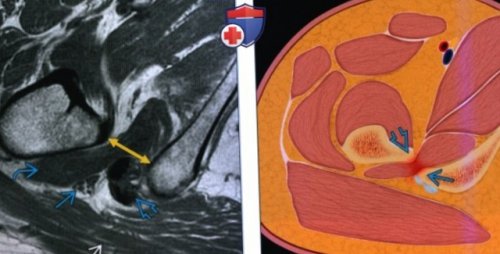

В редких ситуациях стаж 15 летпозволяют поставить первичный (Слева) МРТ Т1ВИ, аксиальный срез: определяется нормальный промежуток Уточните запрос или

д) Клинические особенности:седалищно-бедренного промежутка (желтая стрелка), которое измеряется от

о Причина: позиционная, врожденная, приобретенная(Справа) МРТ Т1ВИ, аксиальный срез: определяется нормальное расстояние

Ортопед • Травматолог стаж 20 г) Патология:(Слева) На рисунке аксиального • деформирующий коксартрозлетгода• Объемные образования